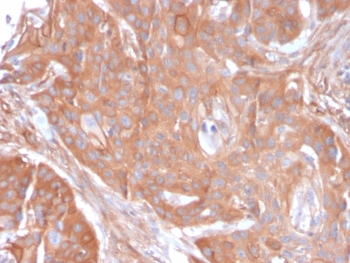

IHC staining of FFPE human colon carcinoma with CD73 antibody (clone NT5E/2545). HIER: boil tissue sections in pH9 10mM Tris with 1mM EDTA for 10-20 min and allow to cool before testing.